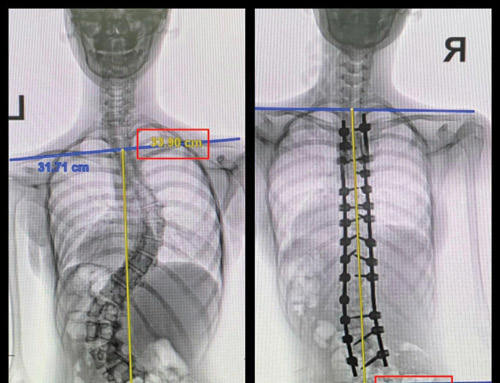

وقال د. خليفة إن المريضة كانت تشتكي من انحناء للعمود الفقري، وتحدب وآلام في الظهر، وصعوبة في الحركة والتنفس، الأمر الذي أدى إلى تغيير نمط حياتها وتقييد حركتها، وفور وصولها إلى المستشفى أخُضعت للتحاليل والفحوصات الطبية الدقيقة، التي بيَّنت إصابتها بحالة انحراف «جنف» مضاعف فوق الـ»70» درجة، ودرس الفريق الطبي الحالة على ضوء نتائج الفحوصات والتحاليل، وخلص إلى ضرورة التدخل الجراحي لعلاج العيوب، والحد من المضاعفات، وبعد اتخاذ التدابير اللازمة، أجريت لها عملية جراحية، تم فيها تقويم العمود الفقري بـ»26» من البراغي وتثبيت ودمج الفقرات، واستخدمت في العملية التي استمرت لـ»6» ساعات، مجموعة من أحدث الأجهزة الطبية التي ساهمت مع الكوادر الطبية عالية الكفاءة والتأهيل بالمستشفى في إنجاحها.

وأكد د. خليفة أن الطفلة بدأت في الوقوف والتحرك في اليوم التالي للعملية، كما أنها استعادت المظهر القويم، بعد تعديل وضعية الحوض والكتف، كما أن طولها مع النجاح الكبير للتعديل زاد «5» سم، وخرجت من المستشفى وهي بصحة جيدة بعد أن أمضت «5» أيام قيد التنويم والعناية الصحية الحثيثة، وتوقع أن تستعيد كامل عافيتها سريعاَ، شريطة أن تلتزم بالبرنامج العلاجي المصمم لها وكذلك إرشادات الفريق الطبي المعالج، وحذَّر د. خليفة من إهمال إصابات الجنف وبيَّن أنها يمكن أن تتسبب في مضاعفات خطيرة، أبرزها: ضغط القفص الصدري على الرئتين والقلب والتسبب في آلامهما، علاوة على ظهور مشكلات الظهر وآلامه المزمنة، بالإضافة إلى تغيير مظهر وقوام المصاب، داعياً الذين تظهر لديهم أعراض انحراف العمود الفقري، إلى التوجه فوراً إلى المستشفيات والمراكز المتخصصة التي تتوفر فيها الكوادر المؤهلة والأجهزة الطبية المتقدمة.